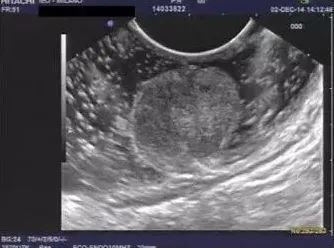

直肠神经内分瘤内镜下是什么样的?

答:多表现为息肉样隆起或黏膜下隆起,经常容易与普通息肉混淆而按息肉切除。

图片

需要做超声内镜吗?

答:直径超过1 cm的直肠神经内分泌瘤需要超声内镜检查明确侵犯深度和排除肠周淋巴结转移,1 cm以内的可以不做。